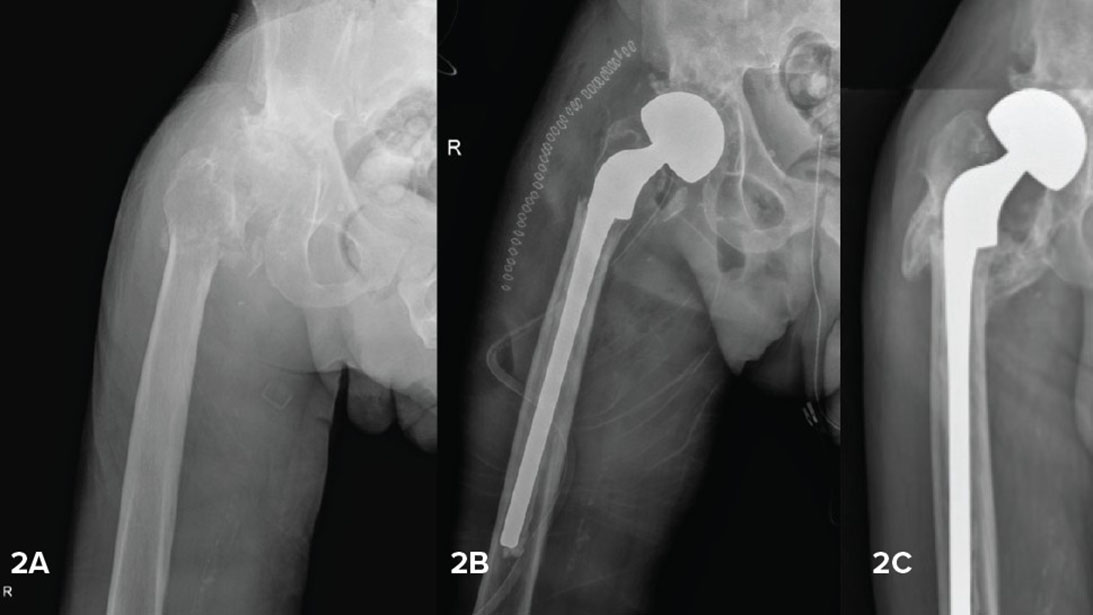

Figure 2. 80-year-old male with new diagnosis of lymphoma of bone with pathologic intertrochanteric fracture (2A). Based on the fracture pattern and Dorr C femoral structure, a long cemented, calcar-replacing stem was used, preserving as much intertrochanteric bone and muscle attachment as possible (2B). Two months postoperatively, following initiation of systemic treatment, the residual bone had healed (2C).

Courtesy of Cara Cipriano, MD